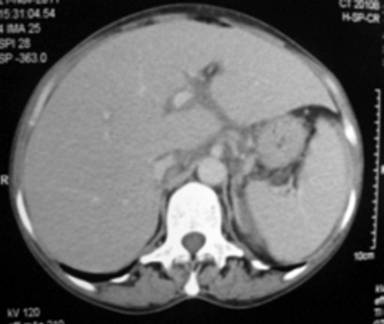

Ultrasonography showed mild hepatomegaly and mild ascites with few subcentimetric lymph nodes in periportal, peripancreatic, aortocaval region and a heteroechoic lesion (3.8x2.2 cm) in relation to pancreatic neck region. Ascitic fluid revealed polymorphic picture with low protein (80 cells per 50 high power field, 80% polymorphs and 20% lymphocytes, sugar 97 mg/dL and protein 1.4 g/dL). Adenosine deaminase of ascitic fluid was 19 IU/L. Contrast enhanced computed tomography (CECT) of abdomen revealed mild hepatomegaly, ascites, few subcentimetric lymph nodes in portohepatic and para-aortic region and a well-defined round to oval lesion, anterior to the proximal body of the pancreas (Figure 2). Esophagogastroduodenoscopy was normal, but endoscopic ultrasonogram (EUS) showed an irregular, predominantly hypoechoic heterogeneous mass in relation to body of pancreas without any invasion into portal vein or aorta. Endoscopy guided fine needle aspiration cytology was suggestive of multiple atypical lymphocytes (Figure 3). Immunohistochemical staining of these cells was positive for CD20, CD79a, and negative for CD5, CD43, and CD23.

|

Figure 2. Contrast enhanced computed tomography (CECT) of abdomen revealed mild hepatomegaly, ascites, few subcentimetric lymph nodes in portohepatic and para-aortic region and a well-defined round to oval lesion, anterior to the proximal body of pancreas. |